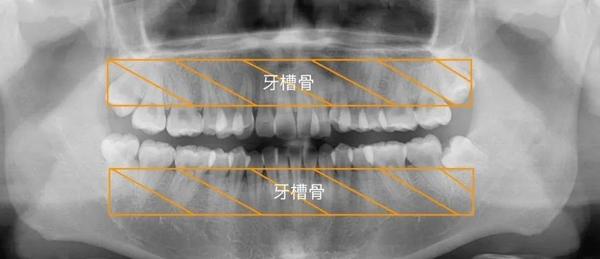

牙齿影像解剖

图片尺寸1080x582